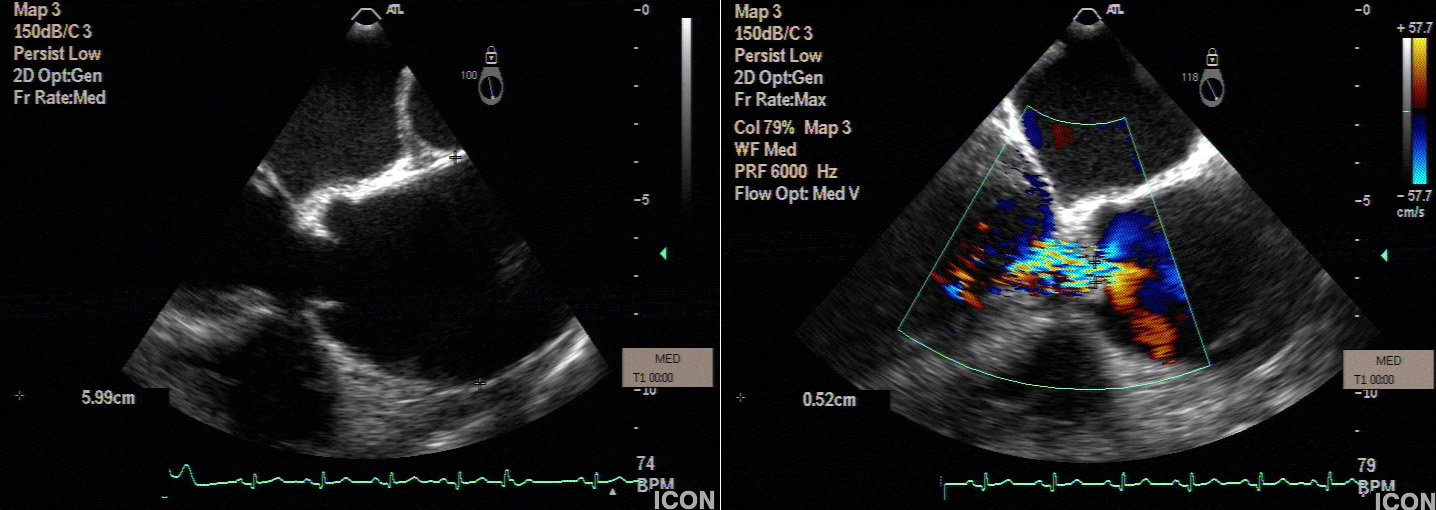

Preoperative echocardiography demonstrated a dilated sinutubular junction (STJ), preserved sinus dimensions and moderate to severe aortic valve insufficiency with central regurgitant jet.